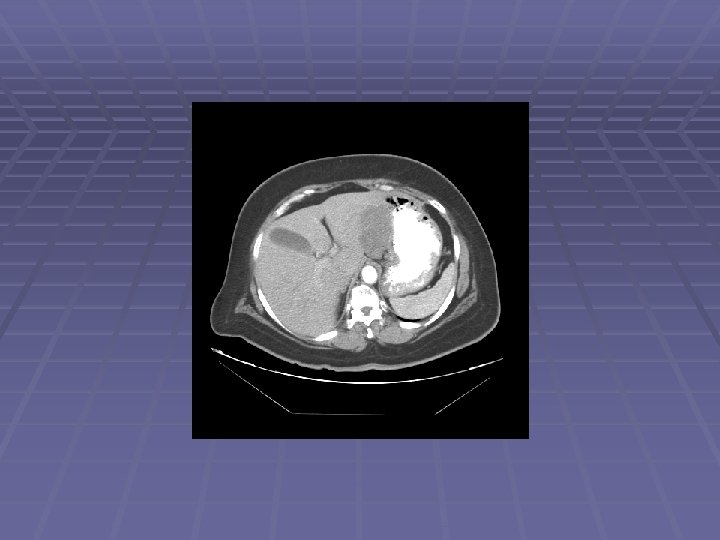

Liver Mass

FNA of Liver Mass

EUS Evaluation of Left Lobe of Liver